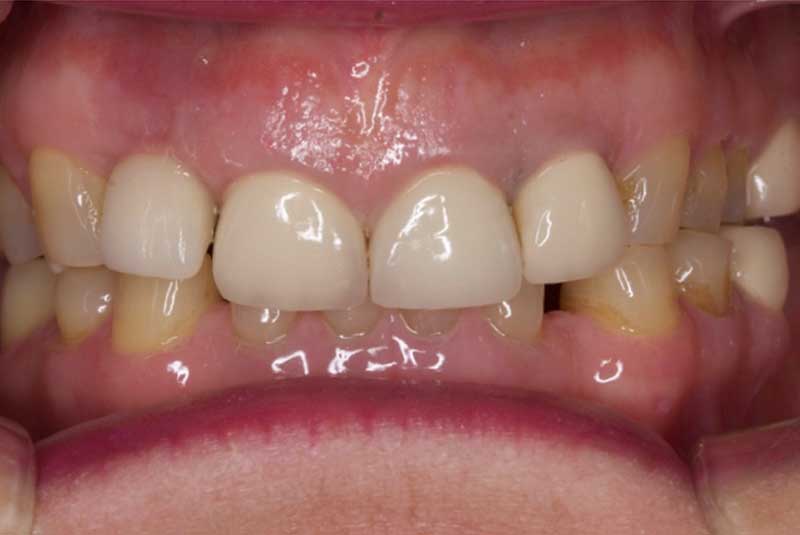

Before & After Veneers (#6,8,9,10,11,12) Crowns (23,24,25,26) Bridge (#27-28p-29), Overlay #21, Implant & Implant Crowns (#7,13,14,15,18,19,20,22), Composite (#3,4,5,12)